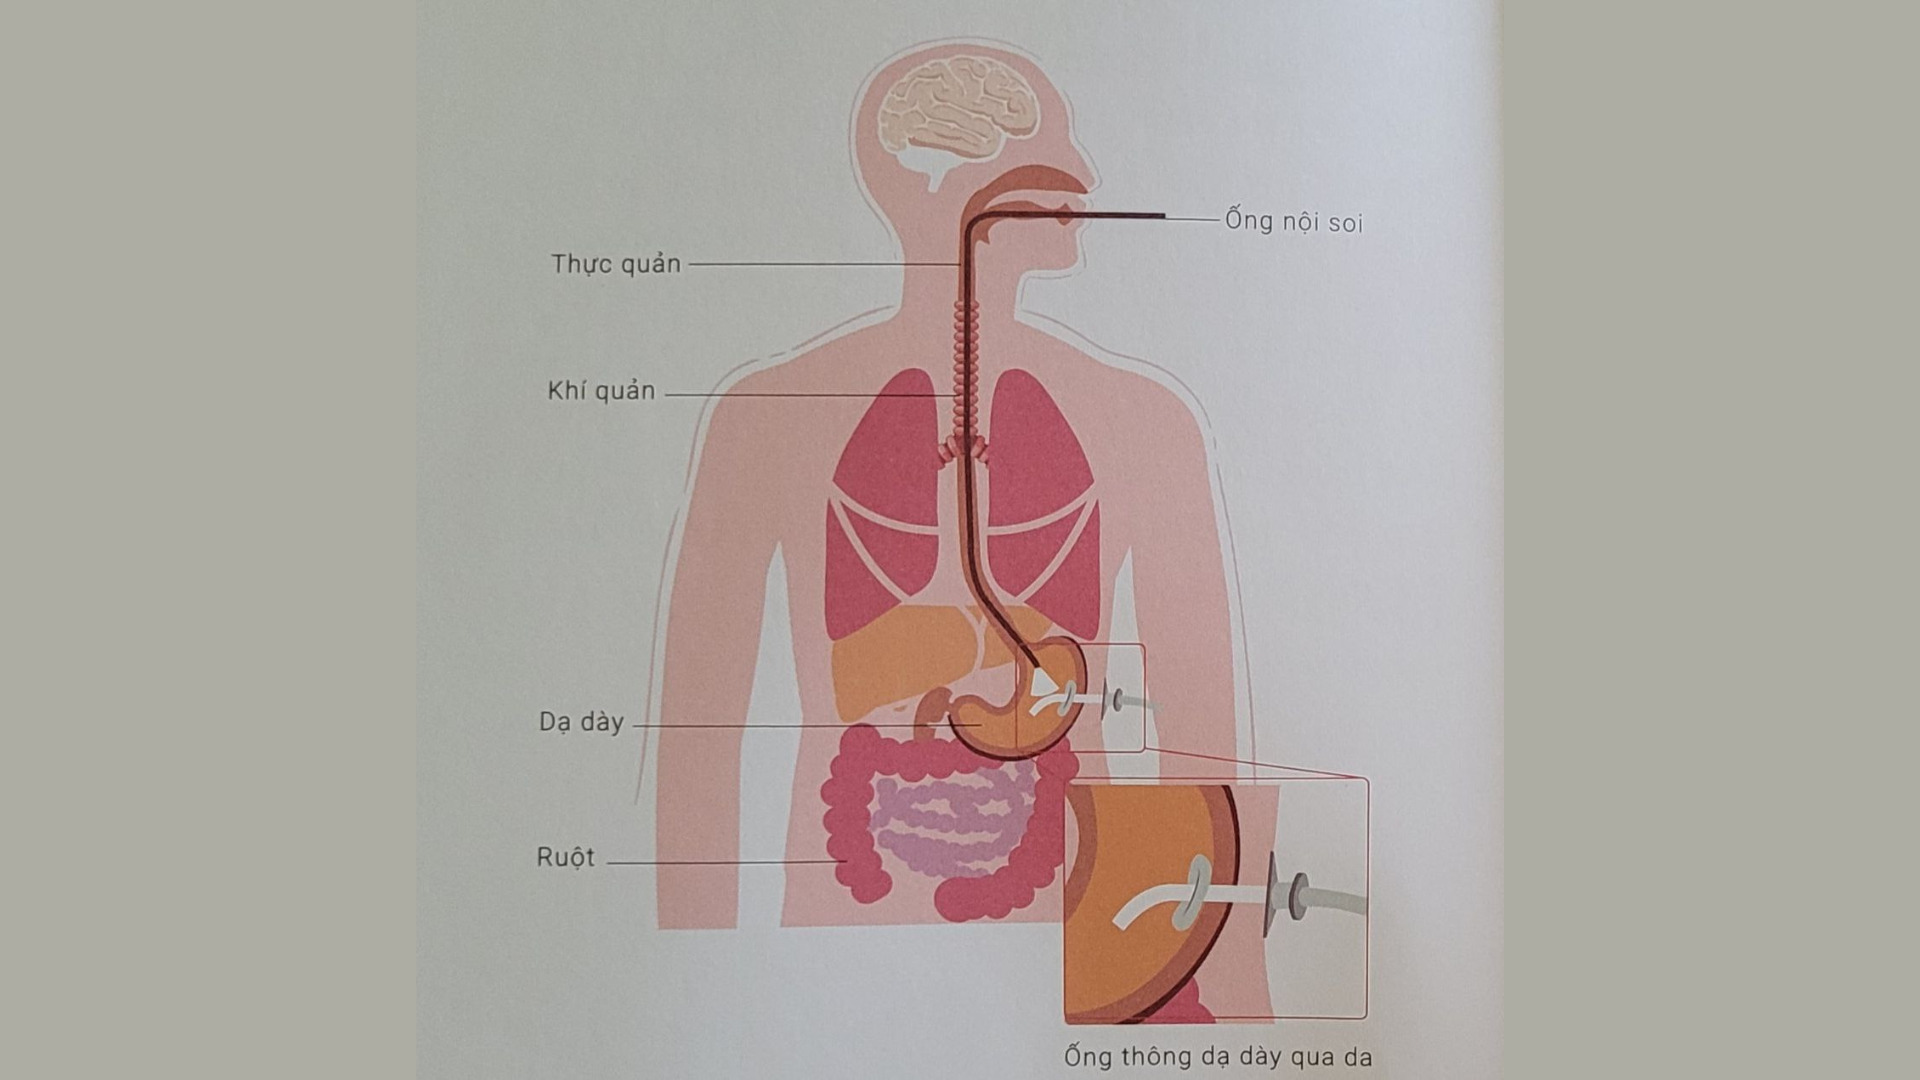

Rối loạn nuốt ở bệnh nhân đột quỵ não

Rối loạn nuốt là một di chứng tai biến mạch máu não rất thường gặp, ngoài việc làm người bệnh khó khăn trong ăn uống, rối loạn nuốt có thể gây ra các biến chứng nguy hiểm như hít sặc, viêm phổi, khó thở và có thể dẫn đến tử vong.